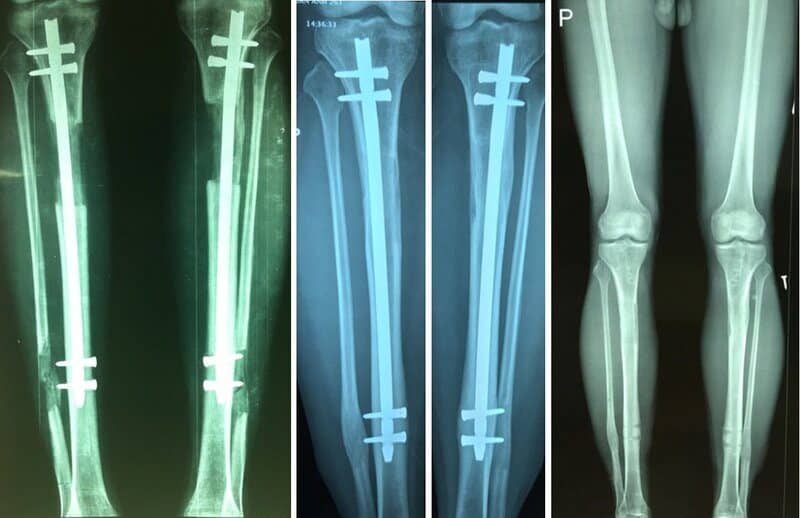

Bước 3: Bác sĩ bắt đầu đóng đinh

Sau khi làm gây mê hay gây tê, bác sĩ sẽ thực hiện rạch một đường ở da cỡ 2cm dọc theo mặt trước gân bánh chè. Sau đó, bắt đầu thực hiện khoan ống vào tủy xương chày và cho một chiếc đinh vào có độ dài ngắn hơn độ dài của xương chày cỡ 4-6cm. Tiếp theo, bác sĩ sẽ rạch da dài 1cm ngay phần cẳng chân trên để đặt dụng cụ định vị, bắt hai vít chốt ngay đầu trung tâm.

Bước 4: Lắp khung cố định nơi cẳng chân

Đặt thiết bị để cố định được vào cẳng chân ở vị trí trên đầu xương chày và đầu dưới xương chày.